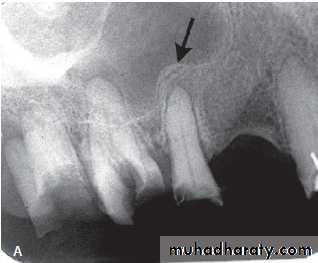

Osteoradionecrosis :

Inflammatory condition of bone (osteomylitis) that occur after the bone has been exposed to high therapeutic doses of radiation for treatment of malignancy of head & neck.*Subsequent trauma (e.g. tooth extraction) or infection may produce osteomyelitis with rapid destruction of the irradiated bone, sequestra formation and poor healing.

Radiographic features: Similar to chronic osteomylitis.

Location: posterior part of the mandible.

Periphery: ill – defined , irregular cortical resorption.

Main radiographic features:

Ragged, patchy or moth-eaten radiolucent areas of bone destruction.

• Occasional evidence of radiopaque sequestra of dead bone.

• Little evidence of healing.

Effects on surrounding structures: Stimulation of sclerosis. No new periosteal bone formation.

Extraction of /6, showing the typical destructive appearance (solid arrow),

resulting in a pathological fracture (open arrow). Radiotherapy had been given several years previously